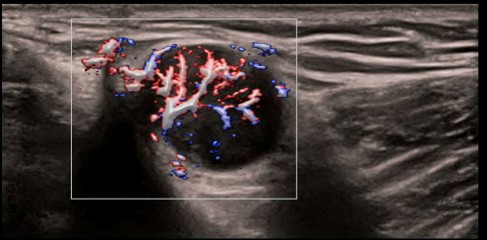

CPP: Vhodné na diagnostiku extrémne jemných prietokov (napr. reumatoidná artritída). Automatická štatistika percentuálneho podielu farebných pixelov v rámci vyšetrovanej oblasti.

CPP: Vhodné na diagnostiku extrémne jemných prietokov (napr. reumatoidná artritída). Automatická štatistika percentuálneho podielu farebných pixelov v rámci vyšetrovanej oblasti.

CPP: Vhodné na diagnostiku extrémne jemných prietokov (napr. reumatoidná artritída). Automatická štatistika percentuálneho podielu farebných pixelov v rámci vyšetrovanej oblasti.